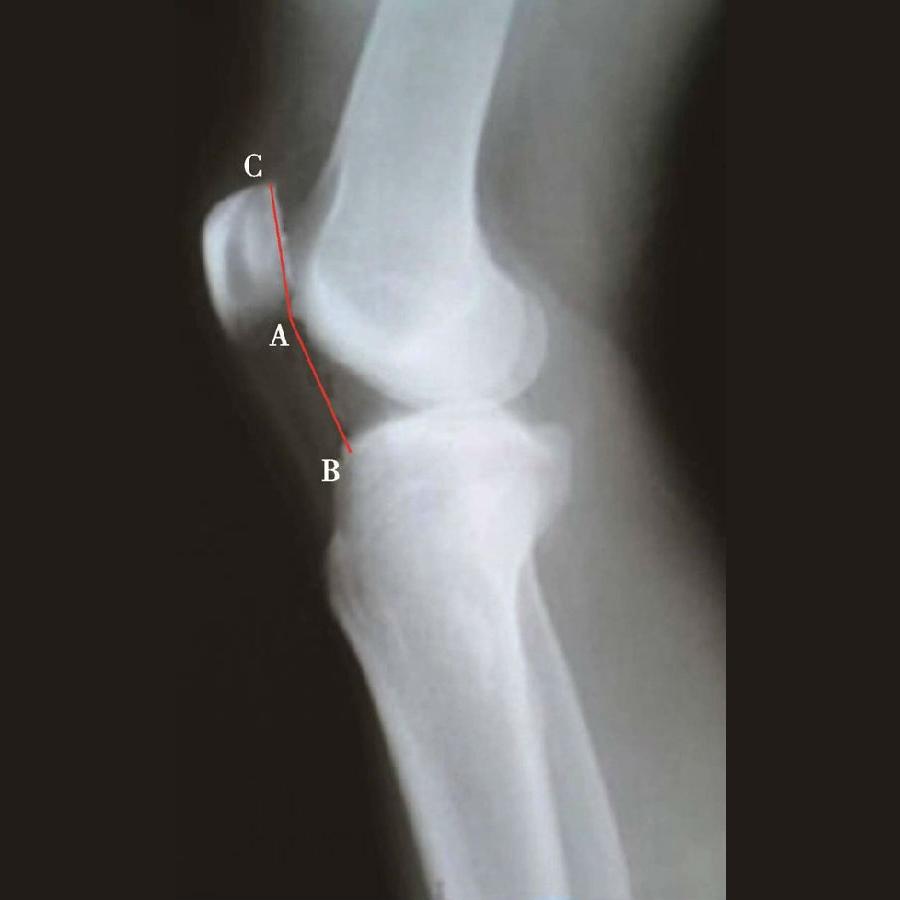

如图示:AB是髌韧带长度,AC髌骨纵轴长度。Insall-Salvati指数=AB/AC(图4)。

图4 Insall-Salvati指数=AB/AC=1.10,为正常髌骨高度

图5 Insall-Salvati指数=AB/AC=1.40,为高位髌骨

但是此法测量髌骨韧带时往往依赖准确的估计胫骨结节与髌骨下极的位置。因此,髌骨下极和胫骨结节的病变都会影响测量的结果,尤其是发生胫骨结节骨软骨炎的患者确定这一位置便更加的困难。此外,该指数不能用于评估胫骨结节向近端或远端移位的效果。因为该指数测量所使用的标记在胫骨结节术后均未发生改变,Insall指数也就不会变化。